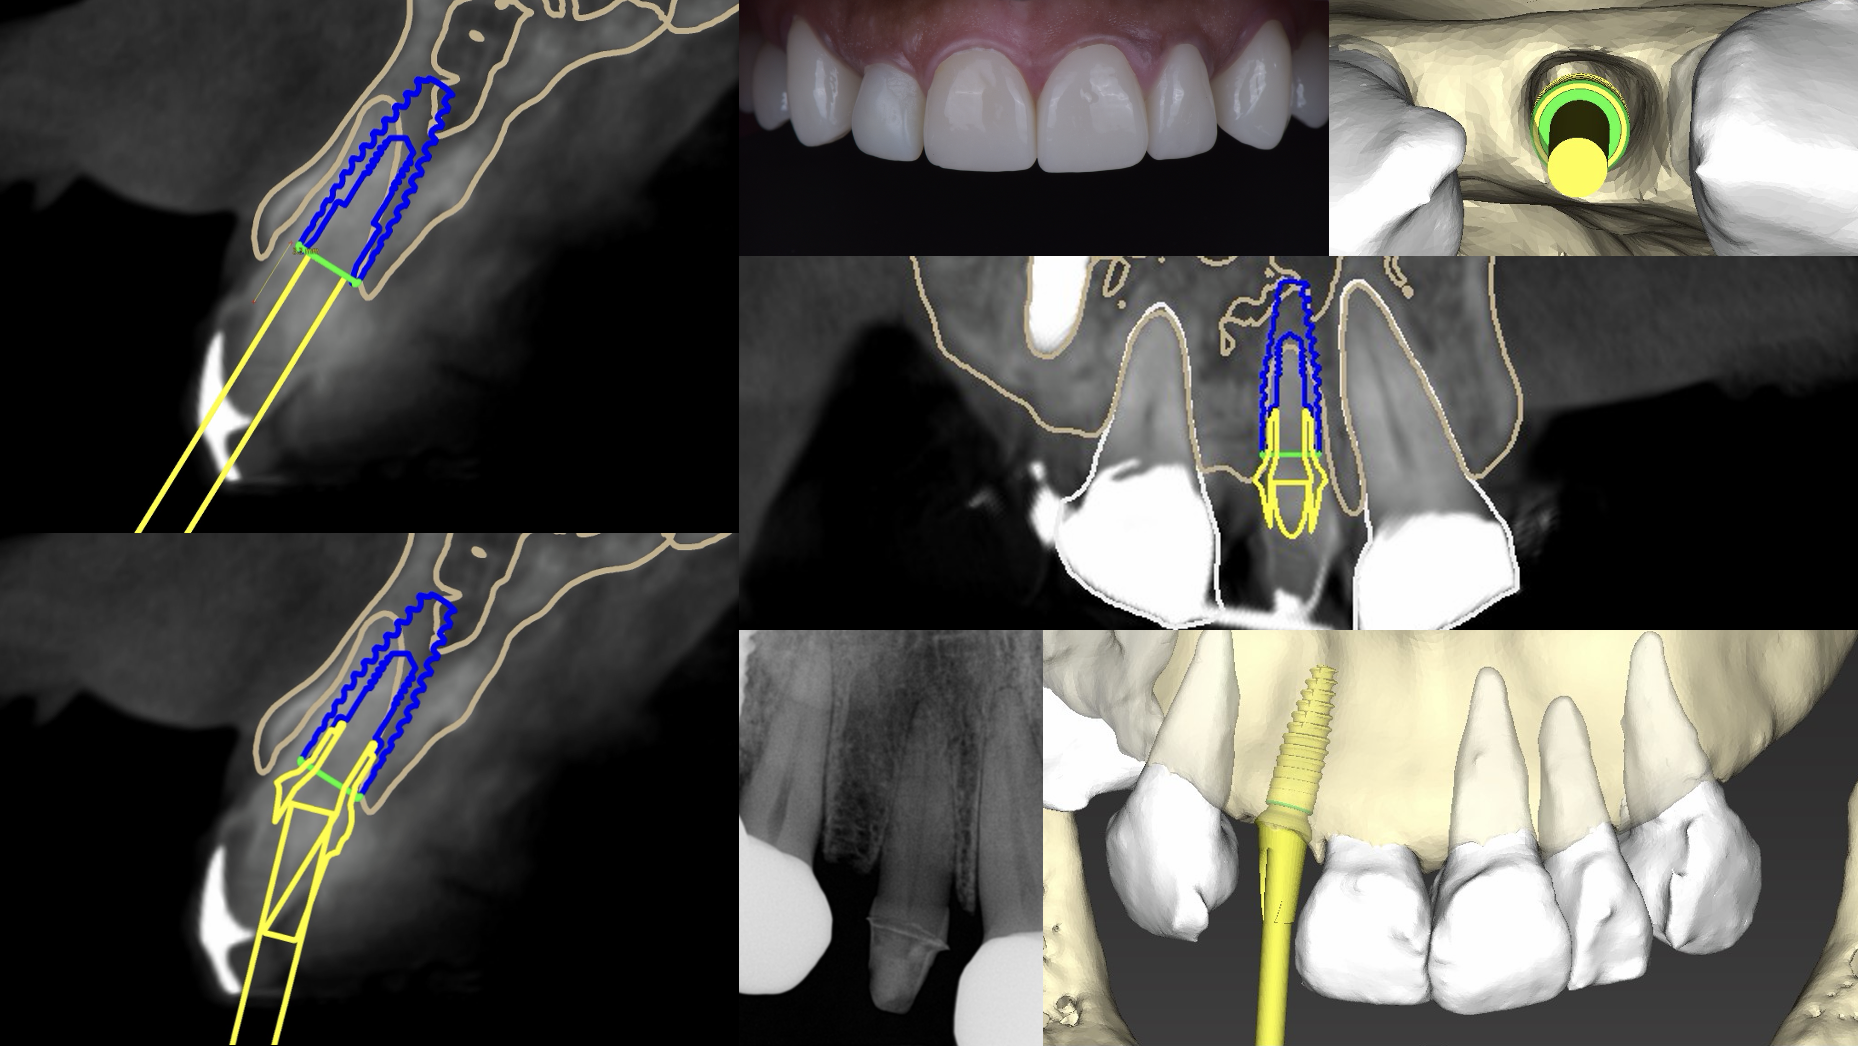

インプラントを検討されている方ですと、 ” CT ”という言葉を聞くことが多いのではないのでしょうか?CTとはまず、3次元的に骨の状態を見るためのレントゲンです。これは追加の検査ではなく、治療の出発点です。インプラントは骨の中に人工歯根を入れる治療なので、歯ぐきの見た目だけでは判断できません。骨の高さ、幅、傾き、神経や血管の位置まで確認して、初めて安全な計画が立ちます。AAOMR(アメリカ歯科放射線学会)は、インプラント部位の評価には断層画像を用い、CTを第一選択とする考え方を示しています。日本の国民生活センターの資料でも、安全で的確な診断のためにCTによる三次元診断が必要と整理されています。

テーマの構造解説|CTで見ているのは「骨があるか」ではなく「どこまで安全に設計できるか」です

CTで確認する内容は、大きく5つあります。

- 骨の高さ:インプラントの長さを決める基礎です。

- 骨の幅:見落とされやすい項目です。幅が足りないと骨を突き抜ける危険があります。

- 骨の質:硬い骨か、柔らかい骨かで初期固定の得やすさが変わります。

- 神経・血管の位置:下顎管やオトガイ孔に近いと、しびれの原因になります。

- 上顎洞との距離:上あごでは副鼻腔に近く、押し込みや穿孔の検討が必要です。

ここで大切なのは、パノラマX線では高さの目安は見えても、厚み(頬側と舌側の幅)が十分にはわからないことです。

たとえば下あごの前歯部は、一見すると骨がありそうに見えても、内側にえぐれた形をしていることがあります。この陥凹を読まずに埋入すると、舌側皮質骨を破って重大な出血を起こすことがあります。2023年の研究でも、インプラント手術の出血合併症では、口底の腫脹、舌の挙上、部分的または完全な気道閉塞が主要な症状として整理されています。

この考え方は、 CTを撮る意味とも直結します。CTで骨だけを見ても不十分です。口腔内スキャンや噛み合わせの情報を合わせて、どの位置なら清掃しやすく、どの角度なら力が偏りにくいかを考えます。2025年の研究でも、ガイド法(ガイドというインプラントオペを安全に行うための装置)はフリーハンド法(術者の経験のみで行う、ガイドを用いない方法)より埋入位置の精度を改善しやすい一方、生存率が上がるわけではないと整理されています。ただ、ベテランの歯科医師がガイドを使わない場合、まだ若い歯科医師がガイドを使ったほうが正確にインプラント手術結果だったというデータもあります。